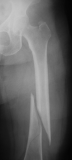

Femur fracture

age 13

Metatarsal fracture

age 16

Tibial fracture

age 57